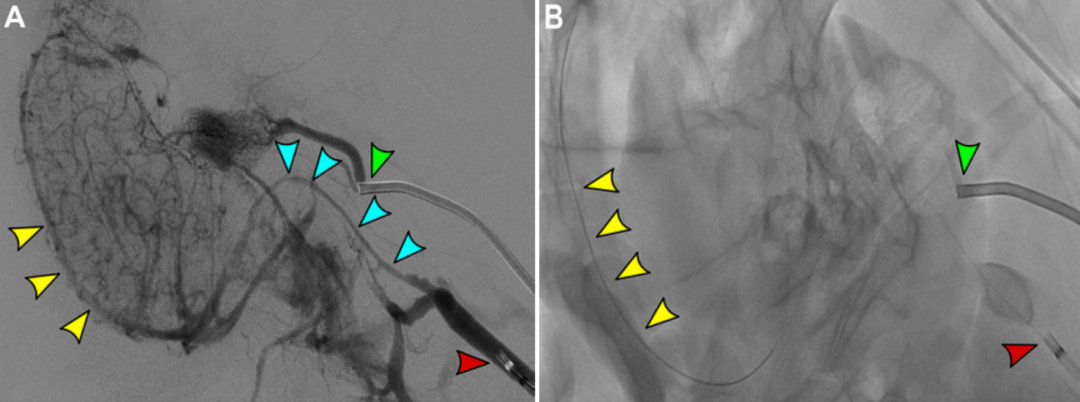

一种用于测试颅内静脉窦血栓机械取栓和血管内成像的临床前模型

图片尺寸813x402

图片尺寸1080x402